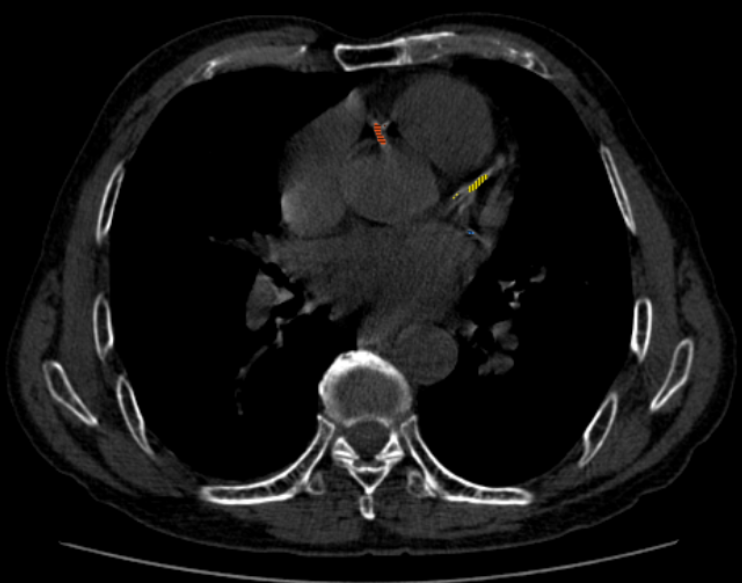

这是一项无创、无需注射造影剂的平扫检查。它就像给血管做了一次“灰度扫描”,数一数上面有多少钙化点。

(1)风险定量:通过数据评分,准确告诉您,您的血管未来10年发生心梗的风险是低、中还是高;

(2)定心丸:如果评分是0分,恭喜您,目前血管里没有钙化病变,短期心血管事件风险极低,可以大大放宽心。